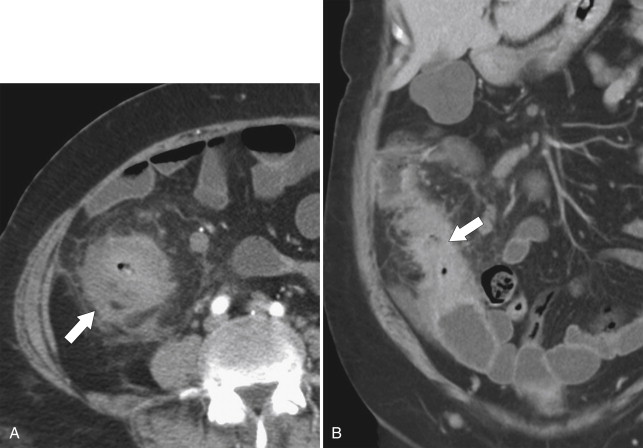

Figure 5-18, Axial ( A ) and coronal ( B ) contrast-enhanced CT in a 61-year-old woman with known ulcerative colitis and now an ascending colon adenocarcinoma ( arrows ) with associated lymphadenopathy ( small arrow ).